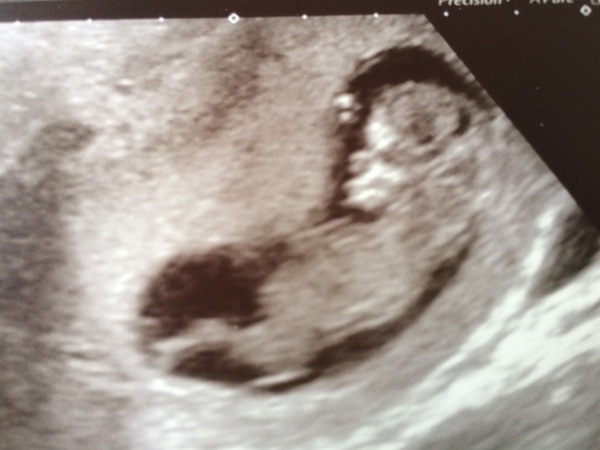

MAY 2017 #3 - Scans and plans !

Scan is all done. EDD is forward by 5 days. The lady doing the scan said the skin at back of the neck looks small so should be ok, just waiting to have my bloods taken.

Baby was misbehaving so took over half an hour to get the measurements, was doing head spins and all sorts. Hope yours went well ghost

Lovely brightsmoke!! Now I've got out, had to see the consultant too who's put my on medicine to help stop my bp going up again.

Well it was absolutely amazing, I can't believe how much it's grown in 3 weeks. And like you brightsmoke I had a naughty one! Despite drinking 800mls of water it wasn't enough so had to go for a walk and drink some more. Baby wouldn't move it's hand from it's face!

Glad yours went well ghost! Mine kept turning it's back to the scanner and moving too much, might as well start as it means to go on, little monster!

Haha Ghost maybe they just don't want us to know yet Wink I do have a pic from the 11wk scan I had, I'll attach that on here too in case it's any better...